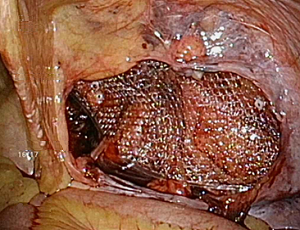

���`�ɂP�Omm�̌��������ē����������Ȃ��̒��ɑ}�����A���ǂɊJ�������i�w���j�A��j���m�F���A���b�V���V�[�g�����ɂ��Ăĕ����܂��B

�����ɂ͂Q�`�R�̂Tmm���x�̏����Ȍ��������Ď�p�{�s���܂����A�����͎�p��A���Ԃ��o�ĂقƂ�ǖڗ����Ȃ��Ȃ�܂��B